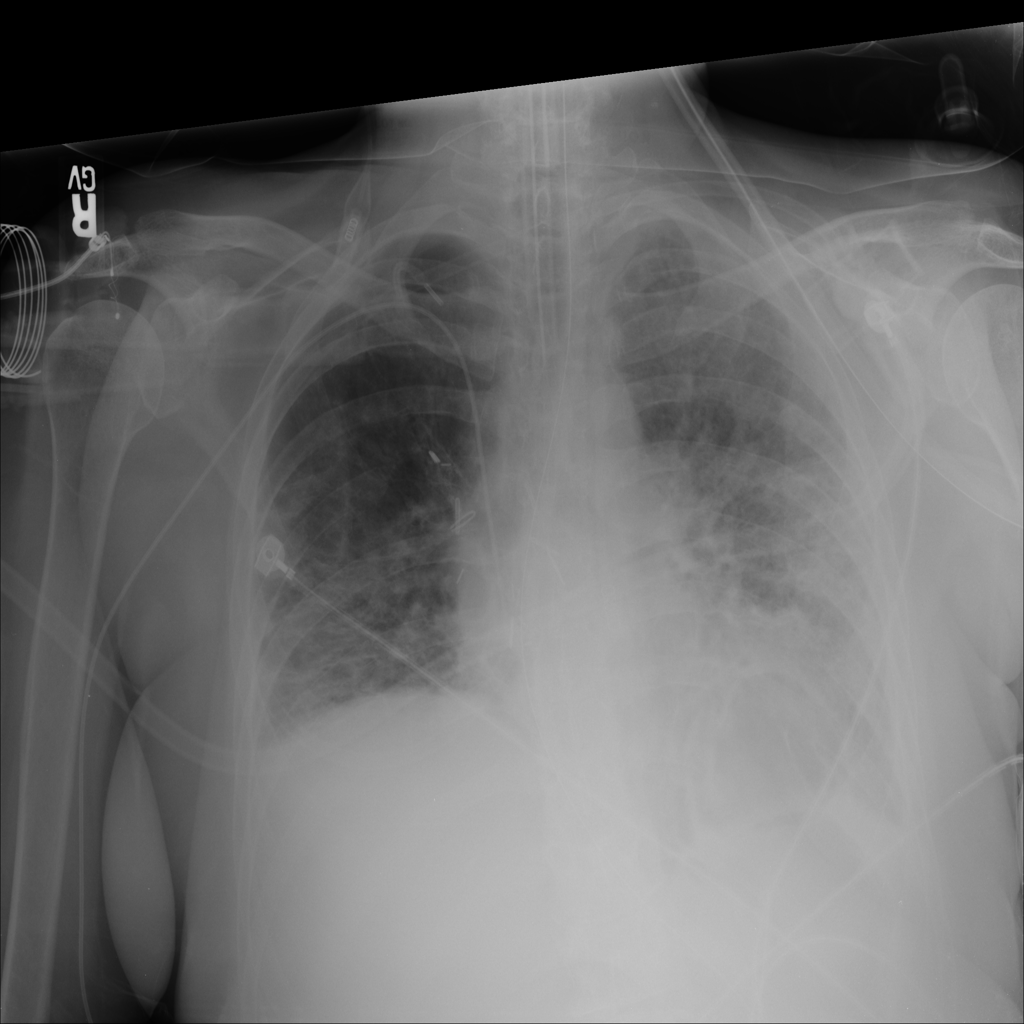

PAT-40F9 · IMG-004Effusion

PAT-40F9 · IMG-004

PA